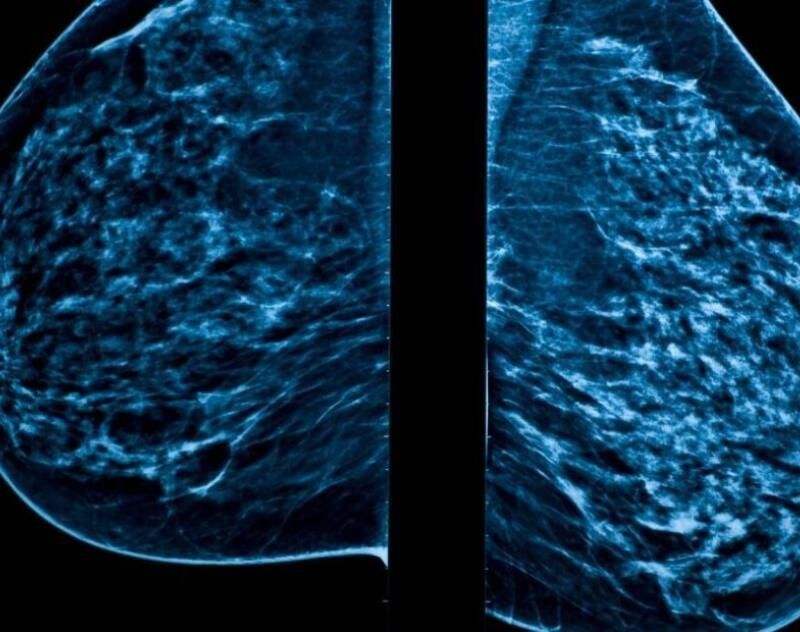

A digital mammography/mammogram is a high-resolution x-ray of the breasts, performed by our experienced and gentle radiographers in Parklane Radiology’s consulting rooms. Mammograms are used to check for breast cancer in women who have no signs or symptoms of the disease. This type of mammogram is called a screening mammogram. Screening mammograms usually involve two or more x-ray pictures, or images, of each breast. X-ray images make it possible to detect tumors that cannot be felt. Screening mammograms can also find microcalcifications (tiny calcium deposits) that sometimes indicate the presence of breast cancer.

80% of breast cancer patients have NO family history/risk factors. Breast cancers often develop in 18 – 24 months meaning that the optimal time interval between mammograms is one year. This timing has been shown in several large studies to decrease the number of fatal breast cancers in the population. Early detection of breast cancer leads to lower-stage cancers at presentation and improved survival!

Thanks to the latest 3D technology, mammograms are pain-free with minimal discomfort.

Early detection saves lives. Mammograms are able to detect breast issues early, to give you the best options to ensure your breasts remain healthy and cancer free.